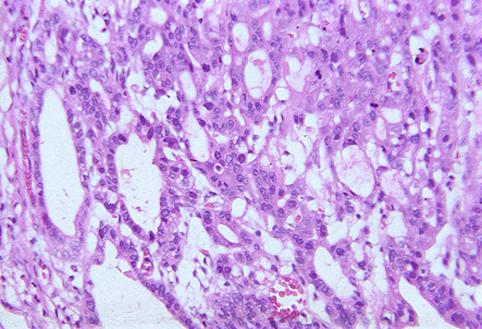

질환(병리주체)의 분류 악성 상피성종양/선암

부위(장기별) 위(부위)/전정

검사방법 마이크로

종양의 육안분류 0형(표재형)/IIa형(IIa+IIc)

종양의 최대경(밀리미터) 25~29

종양의 심달도 m